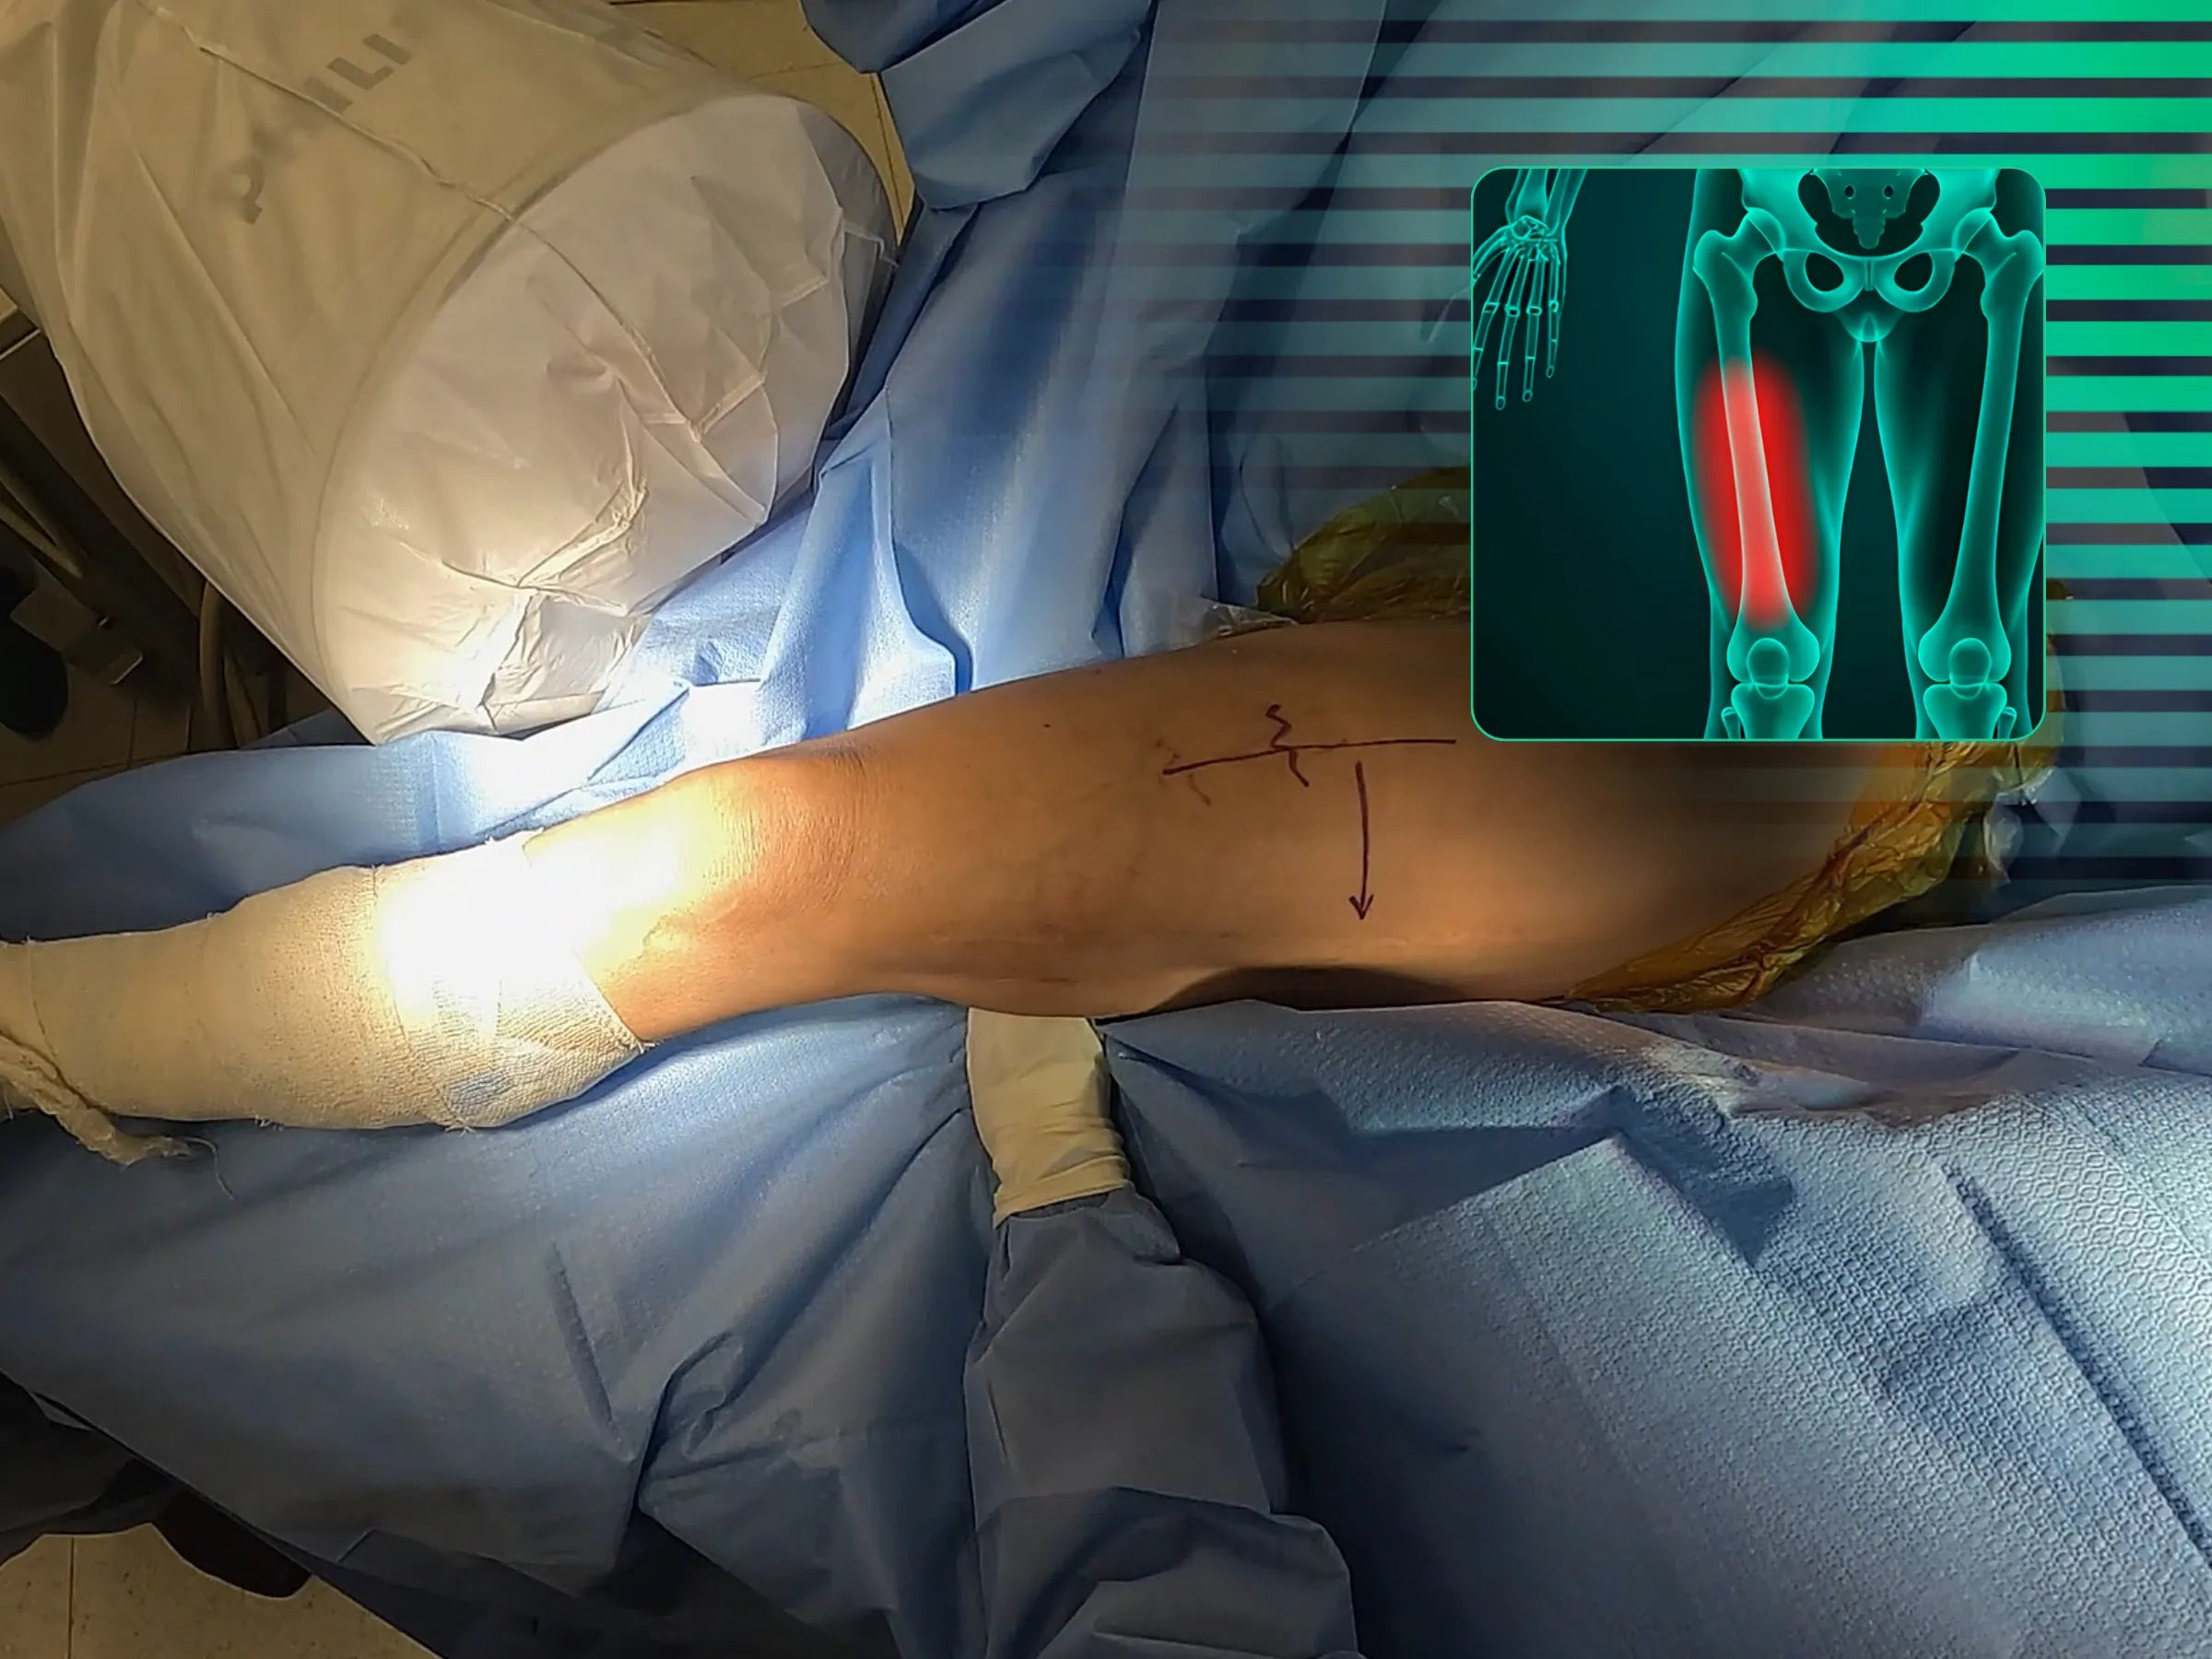

Domine o tratamento de refraturas diafisárias do fêmur, especialmente em casos de fragilidade óssea local, com foco na reabilitação precoce. Este treinamento oferece uma imersão técnica na osteossíntese com haste intramedular anterógrada cefalomedular, enfatizando uma abordagem minimamente invasiva sem o uso de mesa de tração.

- Abordagem minimamente invasiva sem mesa de tração, permitindo manipulação livre do membro.

- Manobras de redução pré-cirúrgicas e durante o procedimento.

- Planejamento e Redução Inicial: Aprenda a realizar manobras de flexão do quadril, rotação externa e rotação interna para programar a redução antes da incisão cirúrgica, permitindo manipulação livre do membro.